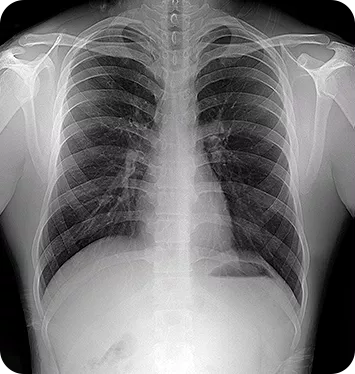

This is a complete system, ready for immediate deployment in any environment. It includes the digital generator, an advanced LG detector, and integrated Artificial Intelligence (AI) for automatic image optimization. Nooka delivers crystal‑clear imaging with minimal radiation dose, making it ideal for mobile units, naval missions, and conflict zones.

The MINE ALNU (Nooka) represents the pinnacle of portable digital radiography technology. This cutting-edge handheld X-ray system is engineered to revolutionize diagnostic imaging for modern healthcare professionals. Specifically, it empowers specialists in orthopedics, sports medicine, podiatry, and veterinary care to capture high-resolution images in any setting. It is, without a doubt, the smarter choice for on-the-go diagnostics.

In addition, the system features the renowned Mine Alnu X-ray generator, which is globally recognized for its consistent and reliable output. Paired with advanced LG detector technology, the Nooka delivers exceptionally crisp and clear images. You can choose between wired or wireless configurations depending on your specific clinical needs. Specifically, this integration ensures maximum diagnostic detail with minimal patient exposure.

- High-Resolution Imaging: Produces exceptional image quality with superior detail resolution